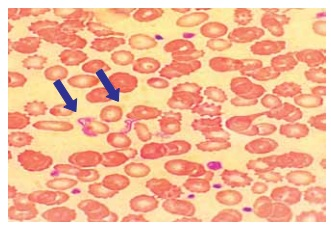

A figura a seguir apresenta um esfregaço de sangue venoso, em que são visíveis formas características de um protozoário flagelado. Esse parasita é transmitido por insetos triatomíneos e está associado a uma doença tropical de grande impacto na América Latina.

Enunciado 4449132-1 (Arquivo pessoal; imagem usada com autorização)

Qual é a doença representada na figura?